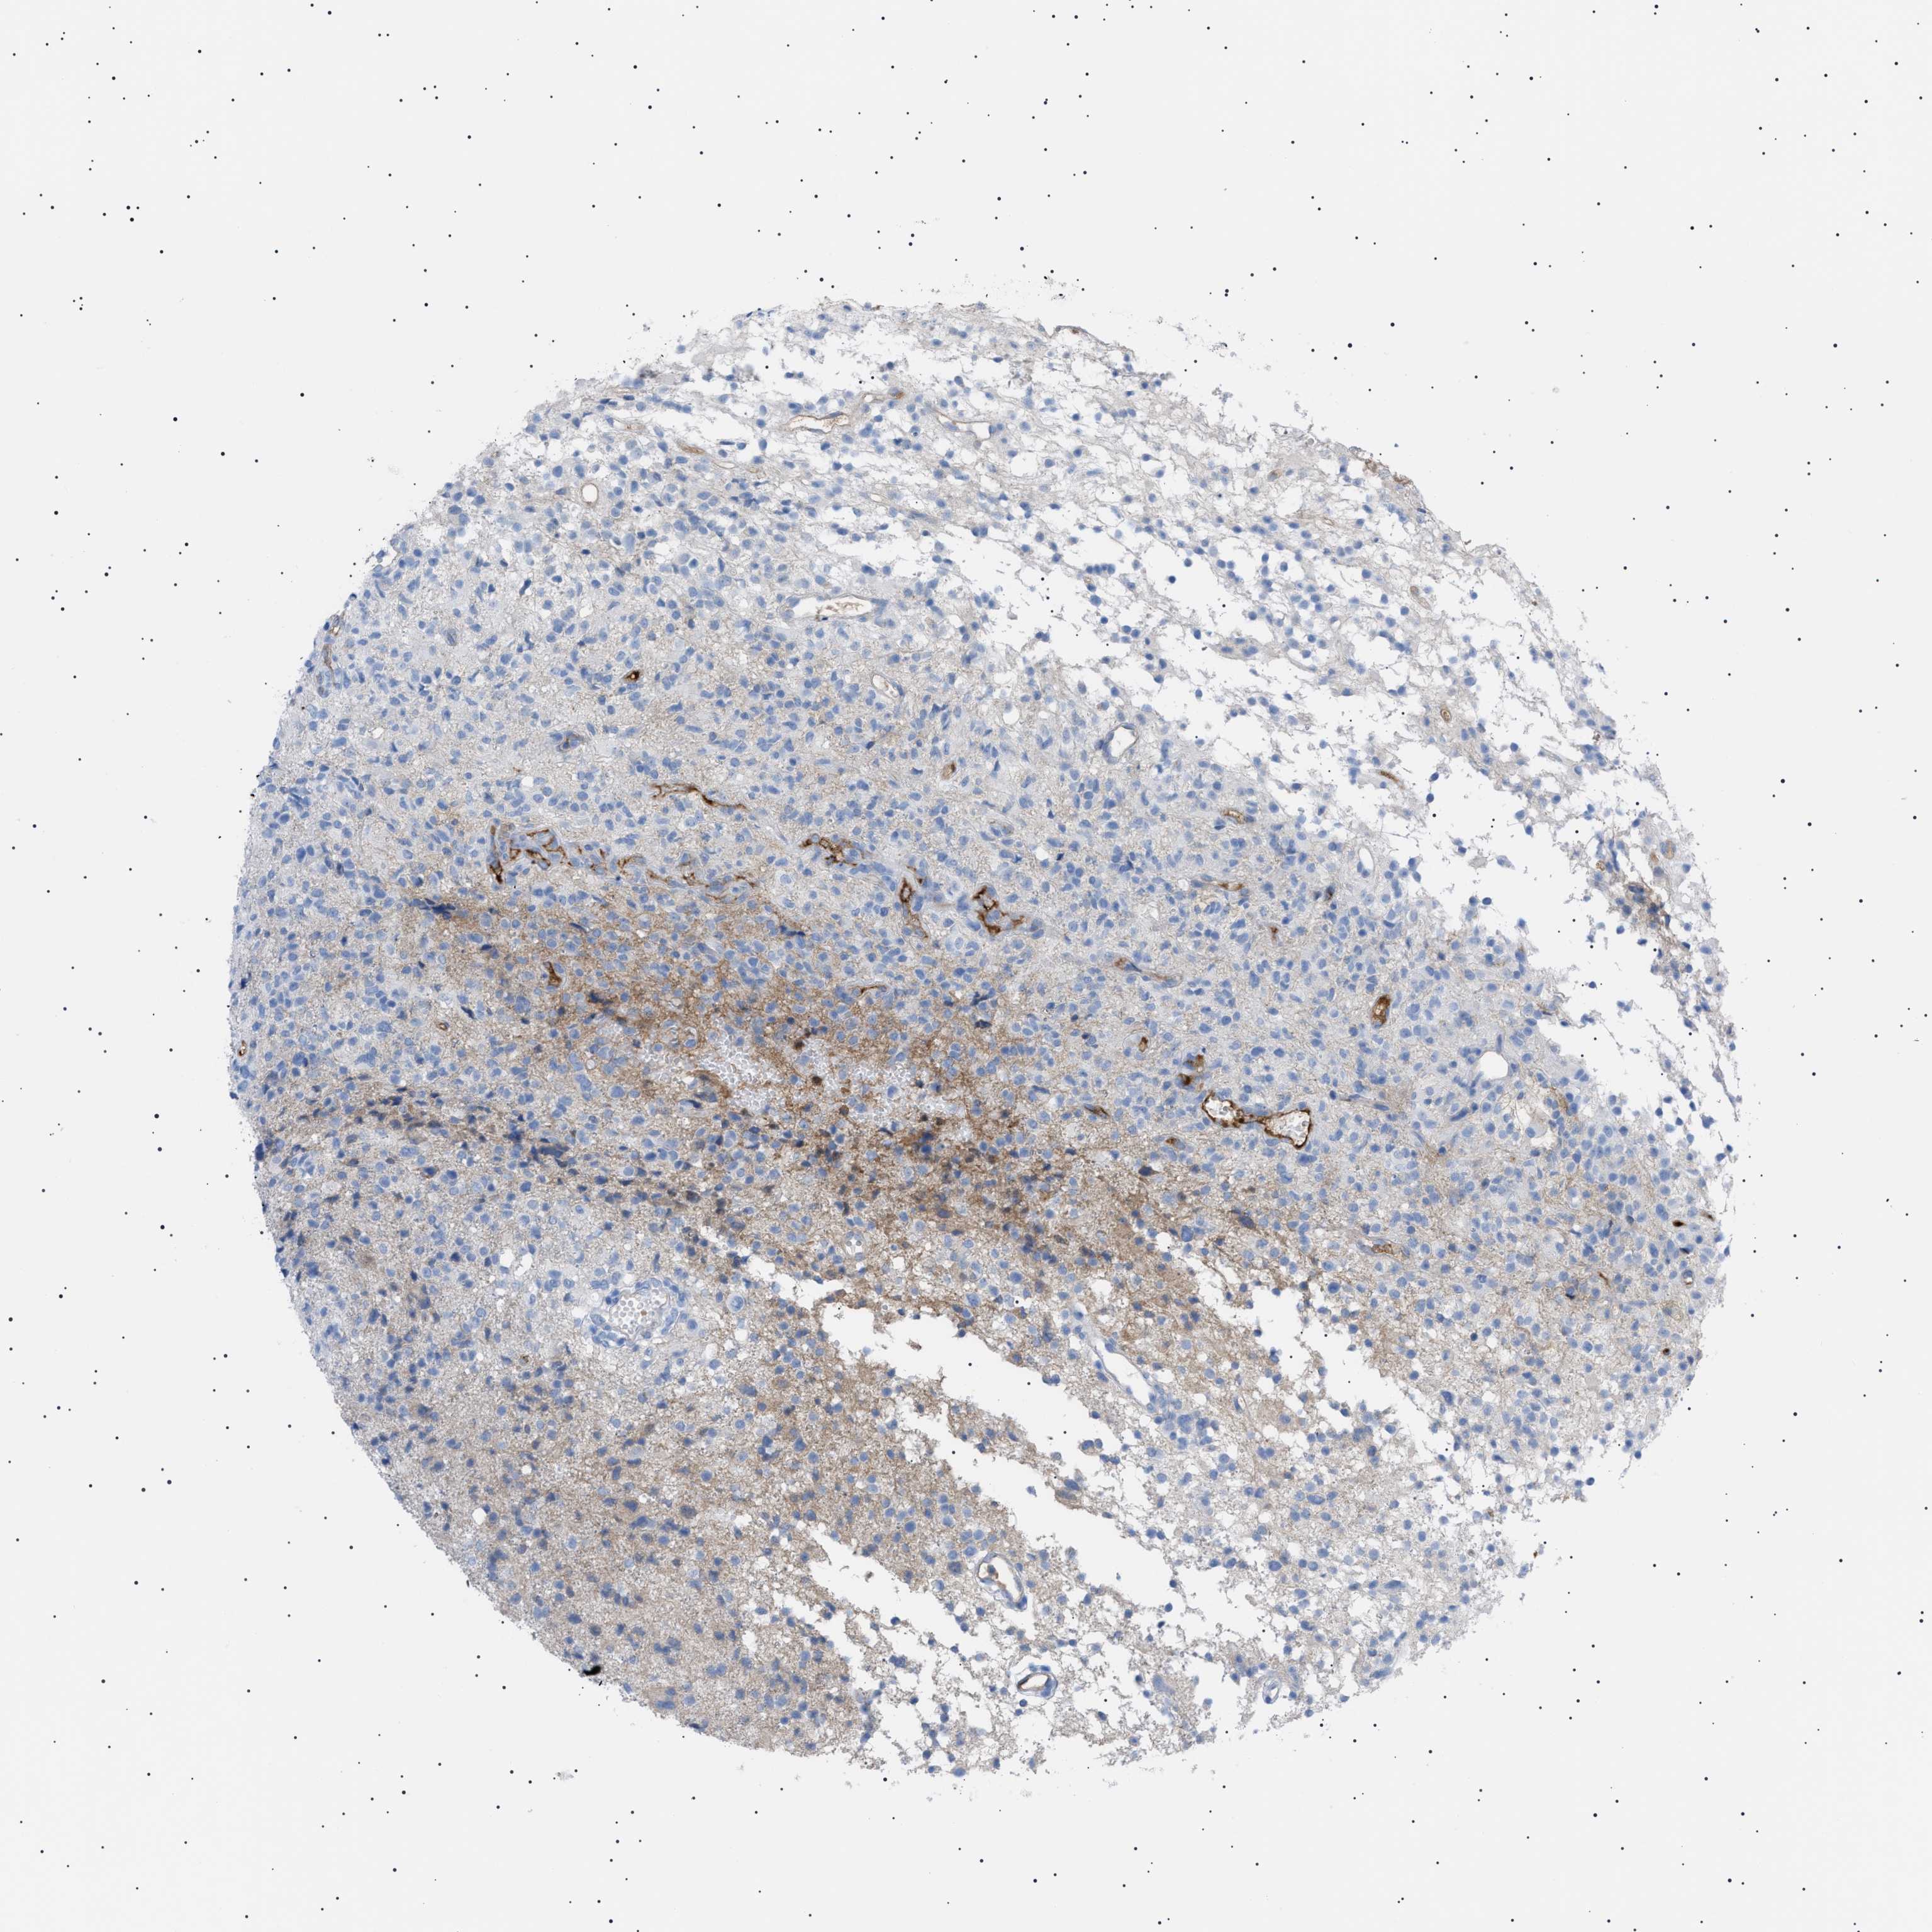

GLIOMA - Protein expressioni

A mouse-over function shows sample information and annotation data. Click on an image to view it in a full screen mode. Samples can be filtered based on level of antibody staining by selecting one or several of the following categories: high, medium, low and not detected. The assay and annotation is described here.

Note that samples used for immunohistochemistry by the Human Protein Atlas do not correspond to samples in the TCGA dataset.

Antibody stainingi

Antibody staining in the annotated cell types in the current human tissue is reported as not detected, low, medium, or high, based on conventional immunohistochemistry profiling in selected tissues. This score is based on the combination of the staining intensity and fraction of stained cells.

Each image is clickable and will lead to virtual microscopy that enables deeper exploration of all samples and also displays staining intensity scores, fraction scores and subcellular localization as well as patient and tissue information for each sample.

Antibody HPA060604

Antibody CAB016072

Staining

High

Medium

Low

Not detected

Intensity

Strong

Moderate

Weak

Negative

Quantity

>75%

75%-25%

<25%

None

Location

Nuclear

Cytoplasmic/membranous

Cytoplasmic/membranous,nuclear

Glioma, malignant, Low grade

Glioma, malignant, High grade